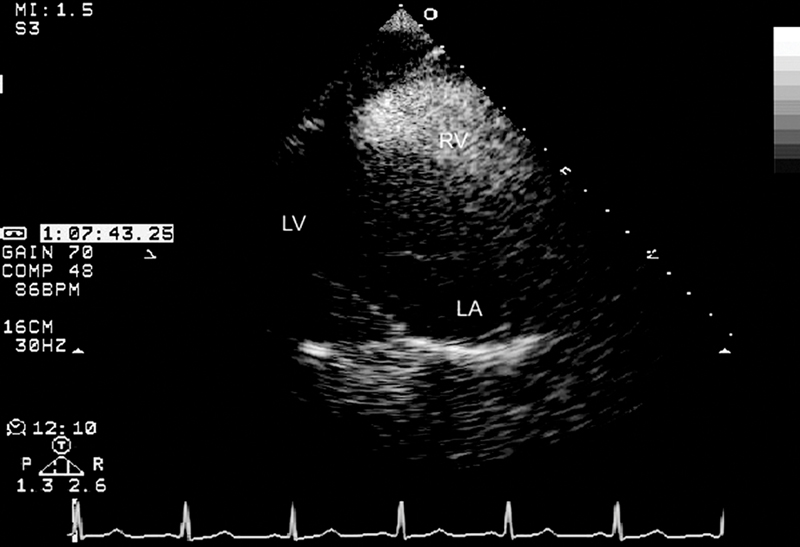

فحوصات تشخيصية لبعض امراض القلب والشرايين التاجية